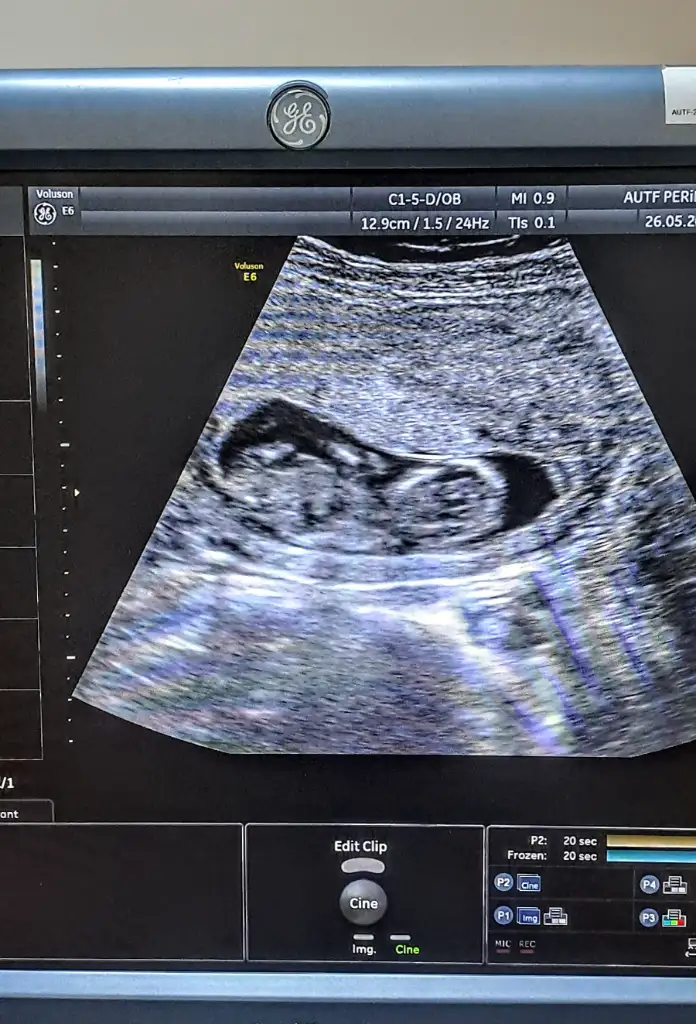

6 haftalık ve 8 haftalik yorumunuzu banada yapabilir misiniz

Eklentiler

• 1000062852.webp

1000062852.webp

27,5 KB · Görüntüleme: 65

• 1000062187.webp

1000062187.webp

29,4 KB · Görüntüleme: 78

Rica etsem bana da tahminde bulunur musunuz? 25 haftalığız hiç sormadım doktorumuzdan😂😊😊😊

• IMG-20250616-WA0039.webp

IMG-20250616-WA0039.webp

14,9 KB · Görüntüleme: 77